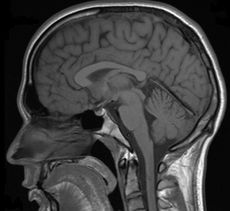

Magnetická rezonance (též MR, MRI, z anglického "magnetic resonance imaging") je zobrazovací technika používaná především ve zdravotnictví k zobrazení vnitřních orgánů lidského těla. S pomocí MRI je možné získat řezy určité oblasti těla, ty dále zpracovávat a spojovat až třeba k výslednému 3D obrazu požadovaného orgánu. Magnetická rezonance využívá velké magnetické pole a elektromagnetické vlnění s vysokou frekvencí. Nenese tedy žádná rizika způsobená zářením. Podstatou barevného odlišení jednotlivých tkání je jejich rozdílné chování při stejném vnějším působení. Jako synonymum bývá někdy používáno výrazu jaderná tomografie, od něho je ale upouštěno, protože mylně vzbuzuje dojem jakési souvislosti s jadernou energií. Více používaná zkratka MRI pochází z anglického sousloví Magnetic Resonance Imaging. Další rozvoj této metody vedl v poslední době k vývoji funkční magnetické rezonance (fMRI) a DTI = DT-MRI. Přístroj magnetické rezonance obsluhuje radiologický asistent.

Na základě naměřeného indukovaného napětí a dalších parametrů je signál pomocí složitých procesů a algoritmů převeden na škálu šedé. Právě kvůli tomu, že výsledný signál závisí na mnoha parametrech, nedá se použít žádné stupnice, která by přesně určila jednotlivé tkáně, proto se k interpretaci obrazů používá spíše rozhraní, na kterých se mění intensita signálu.

Výhodou MRI vůči ostatním zobrazovacím metodám v diagnostické radiologii je větší přesnost při zobrazení většiny orgánů, jež je důsledkem rozdílné intenzity signálu u odlišných měkkých tkání. Navíc toto zobrazení probíhá bez možného škodlivého ionisujícího záření. Některé orgány jako nervy či mozková tkáň bylo možné neinvazivně zobrazovat až právě pomocí MRI. Díky rozsahu nastavení vyšetření je možné dosáhnout rozlišení, které dalece přesahuje možnosti rentgenu či CT. Dalšího zlepšení může být ještě dosaženo podáním kontrastní látky, která pomůže odhalit přítomnost zánětů nebo nádorových tkání. Nový vývoj umožnil zkrátit časový interval získání jednoho snímku na několik milisekund. To umožnilo tzv. MRI-Fluoroskopii, při které jsou pohybující se orgány zobrazovány v reálném čase, což nachází široké uplatnění v intervenční radiologii.